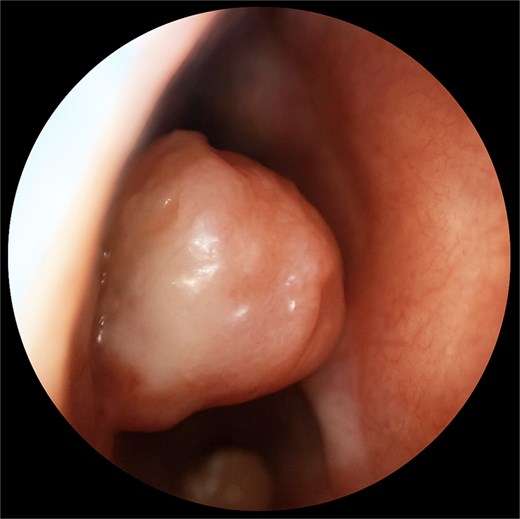

A 67-year-old male presented to our outpatient office with complaints of increasing bouts of right sided nasal bleeding for the preceding twelve months. He had been able to control the epistaxis with pressure and oxymetazoline nasal spray; however, a recent Emergency Room visit for persistent nasal bleeding prompted a referral to our office. The patient denied nasal trauma or other sinonasal problems in the past or present. He was not taking any anticoagulant or antiplatelet therapies. Nasal endoscopy revealed a soft, pale, non tender mass on the caudal end of the right inferior turbinate. Coagulated blood was noted over the anterior portion of this mass, without any vascular prominence or bleeding appreciated over the septal wall. This indicated the nasal mass was the site of recurrent epistaxis. Non-contrast computed tomography (CT) of the sinuses (Figs 1 and 2), showed a soft tissue prominence at the same area seen on endoscopy (Fig. 3).

Differential diagnosis included sinonasal inflammatory polypoid disease, nasal papilloma, sinonasal haemangioma, malignancy, amongst others with a glomus tumour lower on the differential given the rate of occurrence in the nasal cavity. The mass was excised using scissors at its broad base. An oscillating shaver blade was used on the anterior end of the turbinate and an absorbable sponge was placed for hemostasis.